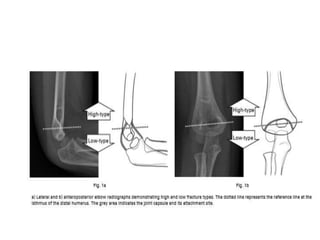

• To determine the level of fracture, a reference line was

defined on the sagittal radiograph at the isthmus of the

distal humerus, and on the AP radiograph as a line con-

necting the medial epicondyle, the olecranon fossa and

the lateral epicondyle.

 High fractures - defined as those exclusively

above the reference line.

low fractures - below or involving the reference

line.